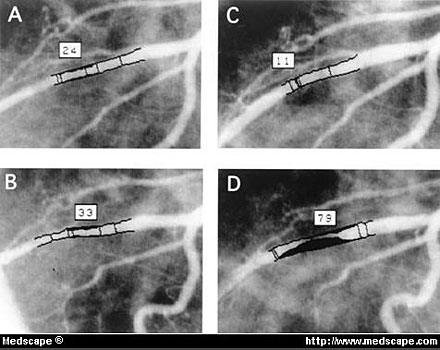

Determination of vessel dimension at site with CMB by quantitative coronary analysis system (same case as demonstrated in Figure 1). A, Before nitroglycerin diameter of middle portion of LAD in diastole was 1.2 mm and diameter stenosis was 24%.

B, In systole, diameter of this portion was 0.9 mm and stenosis was 33%.

C, After nitroglycerin, dimension increased to 1.5 mm and stenosis was 11%.

D, Under these conditions, dimension became significantly narrowed to 0.4 mm and stenosis was 79% in systole.